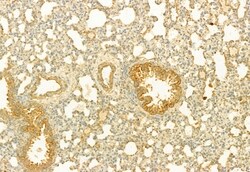

PLCE1 Polyclonal Antibody, Invitrogen™

Antibody detects endogenous levels of total PLCE1.

This gene encodes a phospholipase enzyme that catalyzes the hydrolysis of phosphatidylinositol-4,5-bisphosphate to generate two second messengers: inositol 1,4,5-triphosphate (IP3) and diacylglycerol (DAG). These second messengers subsequently regulate various processes affecting cell growth, differentiation, and gene expression. This enzyme is regulated by small monomeric GTPases of the Ras and Rho families and by heterotrimeric G proteins. In addition to its phospholipase C catalytic activity, this enzyme has an N-terminal domain with guanine nucleotide exchange (GEF) activity. Mutations in this gene cause early-onset nephrotic syndrome; characterized by proteinuria, edema, and diffuse mesangial sclerosis or focal and segmental glomerulosclerosis. Alternative splicing results in multiple transcript variants encoding distinct isoforms.

| Immunocytochemistry, Immunohistochemistry (Paraffin), Western Blot | |

| A synthesized peptide derived from human PLCE1(Accession Q9P212), corresponding to amino acid residues R2267-Q2302. | |

| Human, Mouse, Non-human Primate, Rat | |